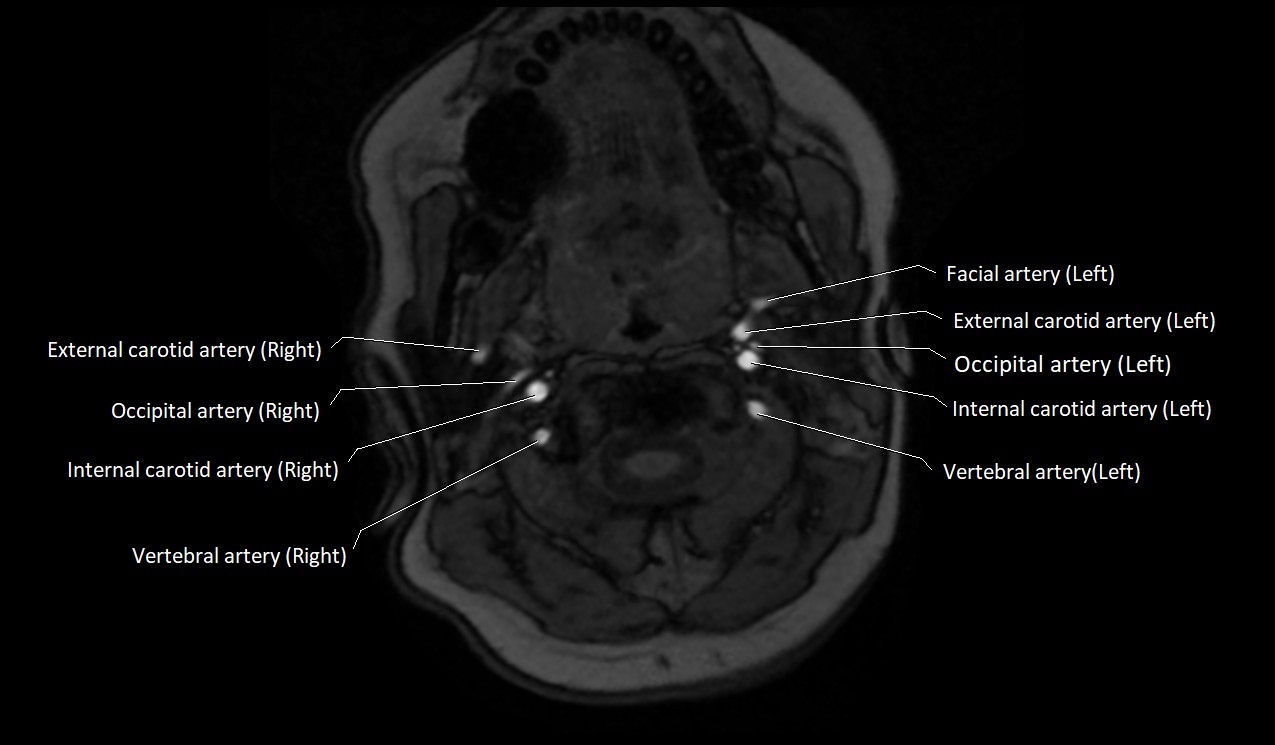

MRI Appearance:

• T1-Weighted Images:

• Appears as a tubular, hypointense (dark) structure relative to muscle

• May show flow void if the blood flow is fast

• T2-Weighted Images:

• Typically hypointense or isointense to muscle, but can be hyperintense if slow flow or stasis is present